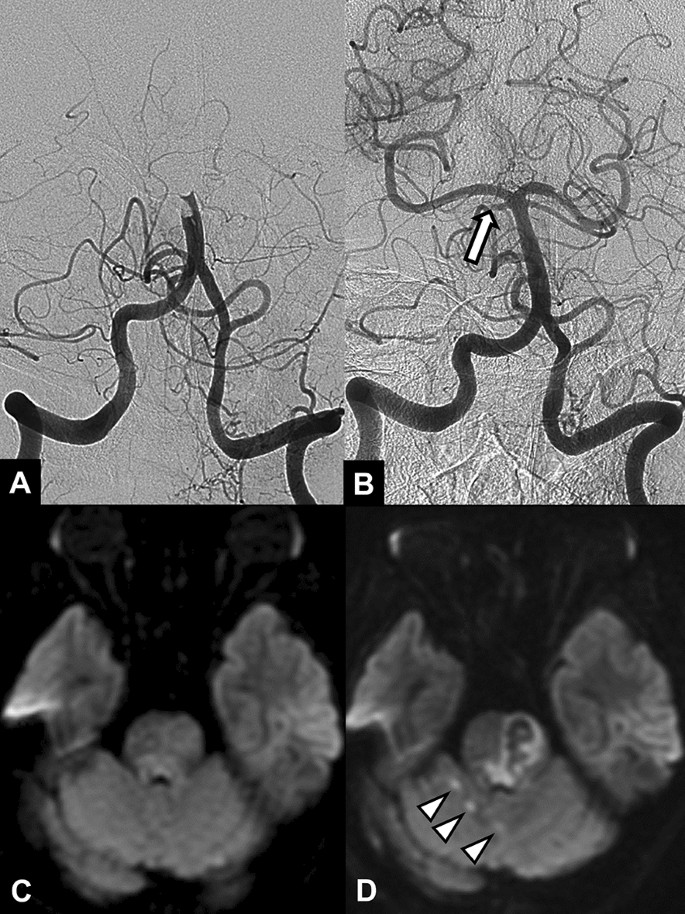

Of 10 patients with remaining SCA occlusions, 5 patients developed a new infarction in the corresponding SCA territory on follow-up DWI. (Fig. 1). All of these infarctions were punctate lesions, 1–3 in number, and 4–11 mm in diameter. Three patients with SCA occlusion showed increased extent of pre-existing SCA territorial infarction and mild mass effect on the fourth ventricle. No cerebellar infarction occurred in the remaining 2 patients. A new midbrain infarction occurred in only one patient, in the posterior region of the midbrain; this patient also had preexisting cerebellar infarction.

A 64-year-old female patient with acute stroke due to basilar artery occlusion. (A) Initial angiogram shows an occlusion at the distal segment of the basilar artery. (B) Final angiogram obtained after stent-retriever thrombectomy shows recanalization of the basilar artery and an occlusion (arrow) in the proximal segment of the right superior cerebellar artery. Pretreatment diffusion-weighted image (C) and follow-up diffusion-weighted image (D) show new punctate infarctions (arrowheads) in the right superior cerebellar arterial territory. Note the brain stem infarction with hemorrhagic transformation in the left half of the upper pons.